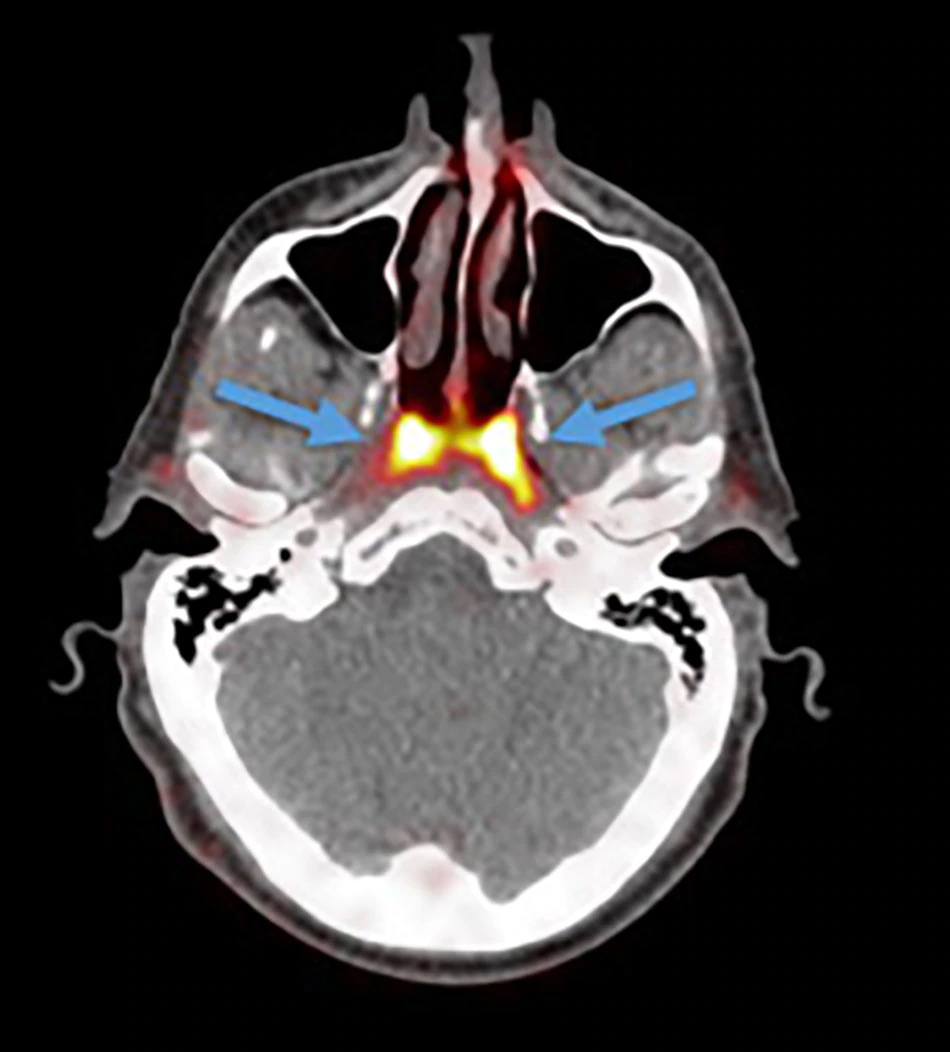

नीदरलैंड के एम्सटर्डम के कैंसर इंस्टीट्यूट के वैज्ञानिक प्रोस्टेट कैंसर की जांच के लिए तैयार किए गए PSMA PET-CT नाम के स्कैन का परीक्षण कर रहे थे। इस दौरान डॉक्टर्स एक रेडियोएक्टिव ट्रेसर को मरीज के शरीर में इंजेक्ट करते हैं। रेडियोएक्टिव ट्रेसर की वजह से ही नए अंग का पता चला। स्टडी में दावा किया गया है कि ये ग्लैंड 1.5 इंच के हैं और ये टोरस ट्यूबेरियस (Torus Tubarius) नाम के कार्टिलेज के एक हिस्से के ऊपर हैं। रिसर्चर्स का कहना है कि शायद इनका काम नाक और मुंह के पीछे गले के ऊपरी हिस्से को ल्यूब्रिकेट करना होगा।

रेडियोथेरपी ऐंड ऑन्कॉलजी जर्नल में छपी स्टडी में रिसर्चर्स ने पुष्टि की है कि करीब 100 मरीजों पर स्टडी में ये ग्लैंड पाए गए हैं। माना जा रहा है कि इस खोज से कैंसर के इलाज में मदद मिल सकती है। अभी तक माना जाता था कि नाक के पीछे के इस हिस्से (Nasopharynx) में कुछ नहीं होता है। वहीं, तीन सलाइवरी ग्लैंड भी जीभ के नीचे, जबड़े के नीचे और जबड़े के पीछे होते हैं, यही माना जाता था।

कैंसर के इलाज के लिए सिर और गले में रेडियोथेरपी के दौरान सलाइवरी ग्लैंड्स को बचाने की कोशिश की जाती है ताकि मरीज को खाने, बोलने या निगलने में परेशानी न हो। अभी तक डॉक्टरों को नहीं पता था कि शरीर में और भी सलाइवरी ग्लैंड्स होते हैं। इस खोज के साथ ही अब रेडियोथेरपी में इन्हें भी बचाने की कोशिश की जाएगी जिससे कैंसर के इलाज में होने वाले साइड इफेक्ट्स को कम किया जा सकेगा।